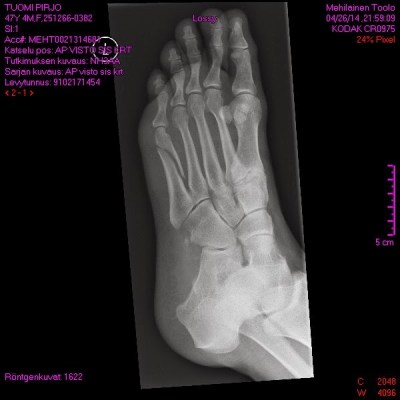

Mutta kotonahan ne suurin osa tapaturmista sitten kuitenkin lopulta sattuu. Tähän asti on harrastuksissa tullut vain pieniä ruhjeita ja mustelmia. Kotona rapuissa hosuessa murtui jalka. Aika helposti vielä. Ei ollut tukevat vaelluskengät jalassa. Sukka on vähän liukkaampi kuin vibram. Tavarat on sikin sokin käsissä eikä repussa. Ja sitten vielä vähän vauhdikkaammin rappusia alas, niin siinä sitä ollaan.